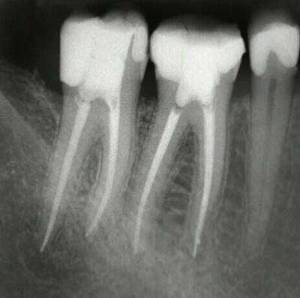

Es una de las técnicas más complejas y laboriosas de la Odontología conservadora, que trata de limpiar y sellar (momificar) los conductos dentarios en dientes con patología pulpar (del nervio) ya sean pulpitis o necrosis pulpar (nervio necrótico).

La endodoncia es uno de los tratamientos más complejos y con mayor riesgo de fracaso de la Odontologia, que requiere unas manos expertas con una técnica muy depurada que sólo puede garantizar un especialista en la materia. Se efectúa el tratamiento biomecánico y la desinfección de los conductos radiculares con diferentes substancias químicas y con limas de diferentes tamaños, para acabar sellando todos los conductos con un material inerte biocompatible que debe llegar hasta el ápice dentario.